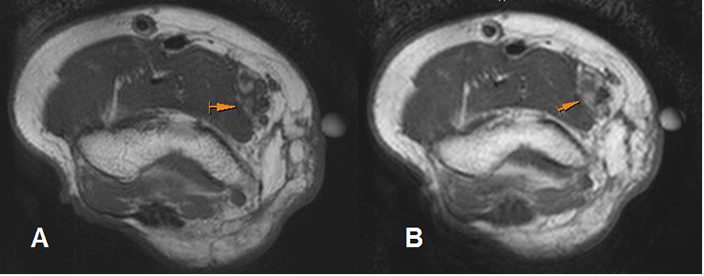

Fig 205. Cambios PostQx.

A: RM axial en T1 simple y B: RM axial en T1 con contraste. Seguimiento de resección de un sarcoma pleomórfico indiferenciado. Hay leve realce del contraste en la parte medial, que resultó ser fibrosis residual.